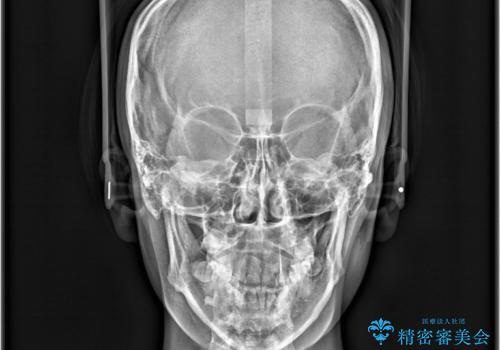

- 「歯の捻じれとがたつき」を主訴に来院された患者様です。

軽度な捻転と叢生だったため、インビザラインのモデレートで治療を行いわずか半年で治療を終える事が出来ました!